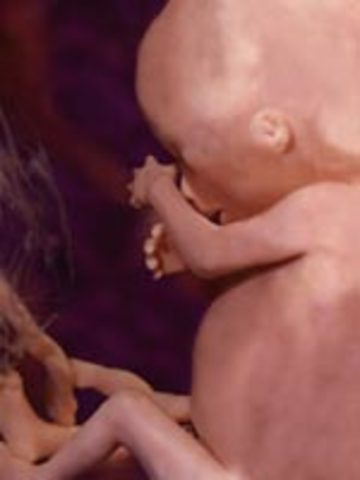

• week 25

Sexual organs fully developed. Brain cells are starting to mature.

• week 26

week 26

Baby's eyes beging to open. Coordination so the baby can suck on his thumb